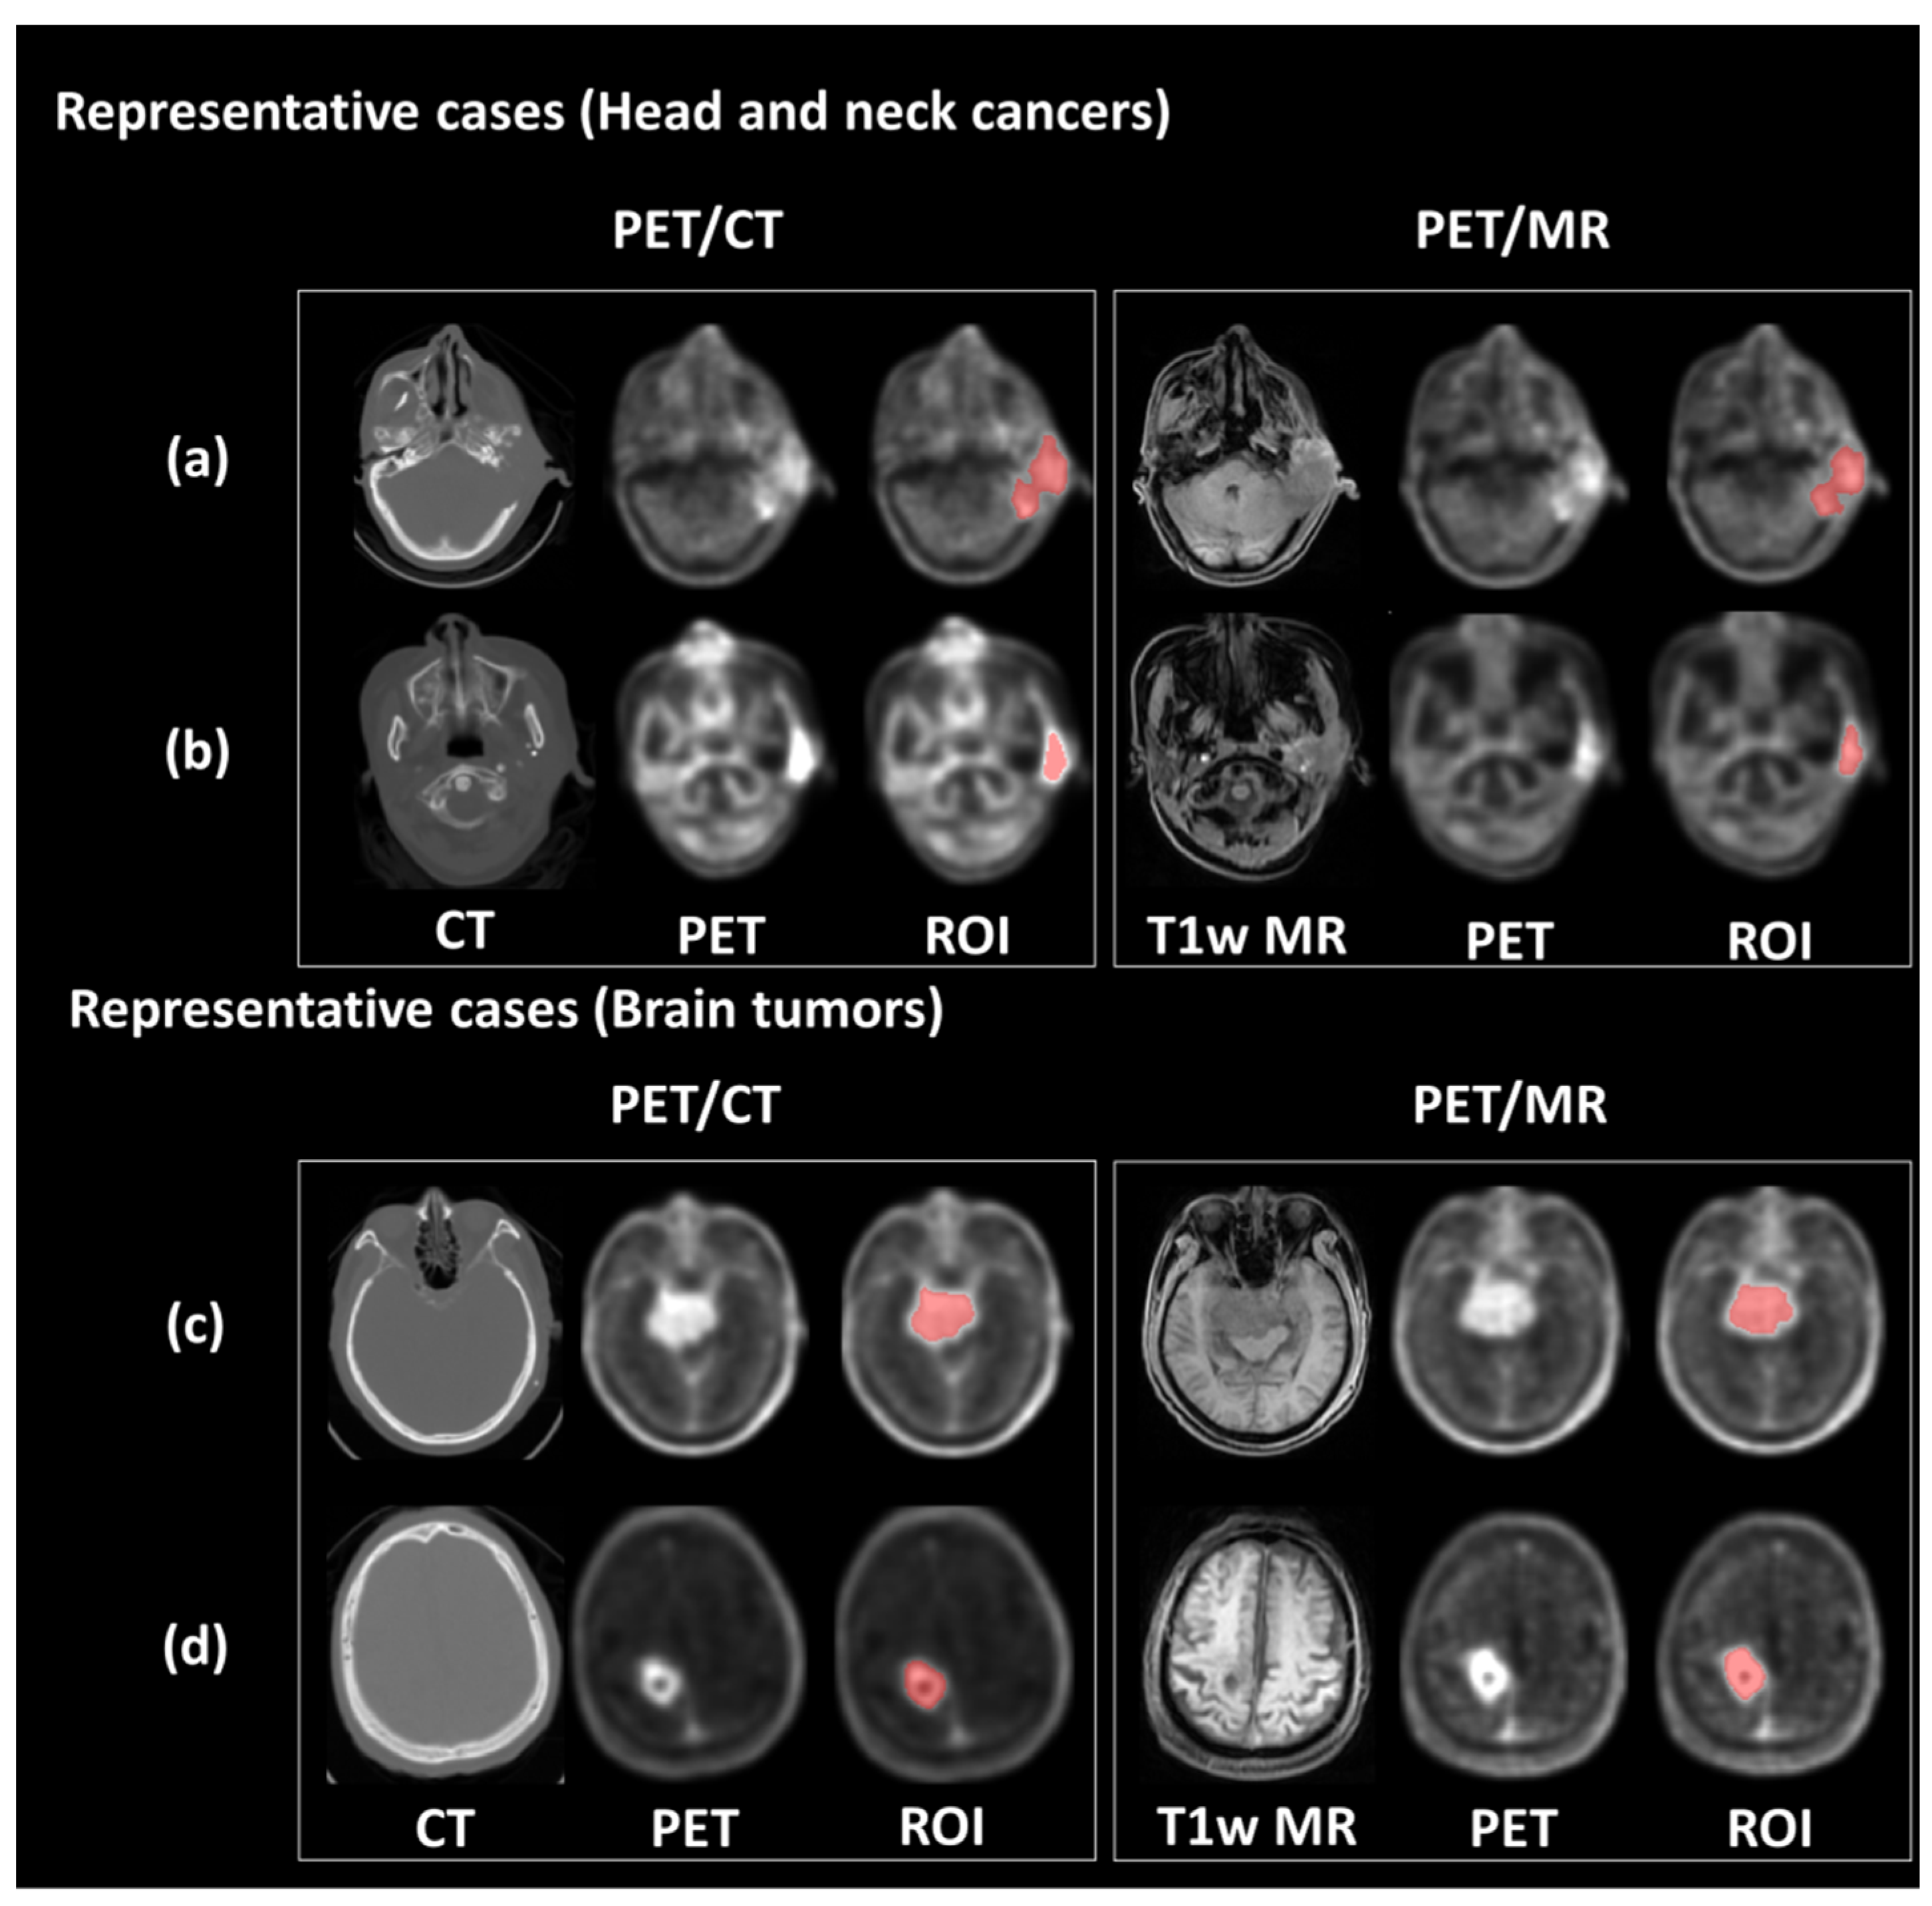

2.1. Patient Cohort

3. Results

3.1. Clinical Characteristics of Patients